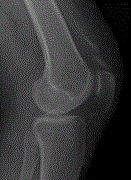

Calcific tendonitis of the quadriceps tendon

S A Webb and others

Journal of Surgical Case Reports, Volume 2018, Issue 4, April 2018, rjy053, https://doi.org/10.1093/jscr/rjy053